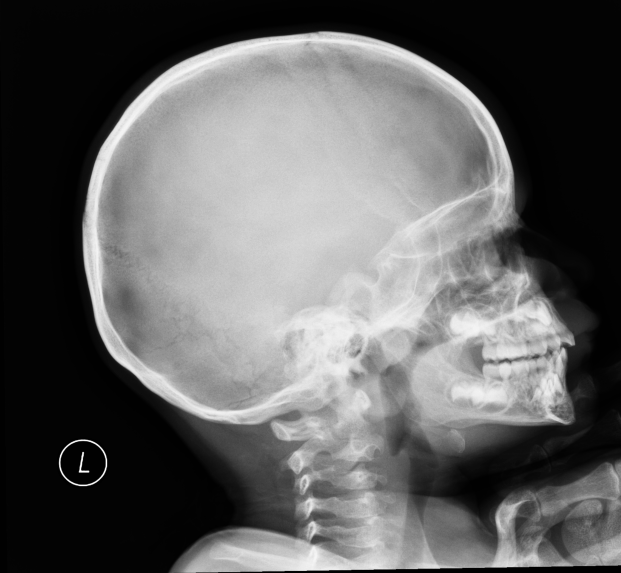

Abnormal fr lt mand condyle |

Abnormal Left mandibular condyle fracture |

Correct |